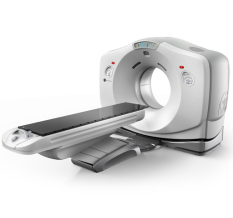

32-Срезовый компьютерный томограф SinoVision InsitumCT 338

InsitumCT 338 - мультисрезовый компьютерный томограф на 32 среза для рутинных и углубленных диагностических обследований, малоинвазивных вмешательств под контролем КТ. К ключевым особенностям рентгеновских сканеров компании SinoVision относятся: пониженная лучевая нагрузка, ускоренное сканирование с получением четкого и детального изображения, что позволяет выявлять мелкие патологические изменения в любой части организма человека.

- Количество физических срезов: 16/32

- Минимальная толщина среза: 0,625 мм

- Мин. время оборота рентгеновской трубки: 0,5 с.

- Диаметр апертуры гентри: 76 см